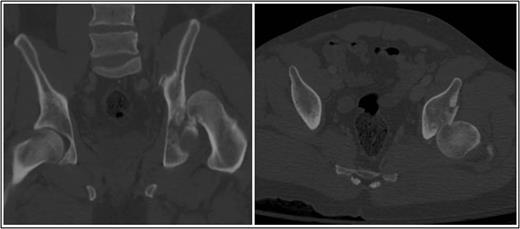

A 35-year-old male was involved in a high-speed urban dirt biking accident. The patient was stable with a GCS of 15 and was neurovascularly intact. His left knee exhibited a 10 × 20 cm medial traumatic arthrotomy and his thigh compartments were soft and compressible. Imaging revealed a left hip postero-superior dislocation, posterior wall acetabular fracture, ipsilateral transverse femoral diaphyseal fracture and an engaging hill-sachs-type lesion of the femoral head with the postero-superior acetabulum (Figs 1–3). Cefazolin, gentamicin and tetanus prophylaxis were administered along with a bedside washout of the traumatic arthrotomy. The patient was medically cleared for operative intervention as all blood work and further imaging were normal.

Coronal and axial CT pelvis of the left femoral head engaging with the postero-superior acetabulum.